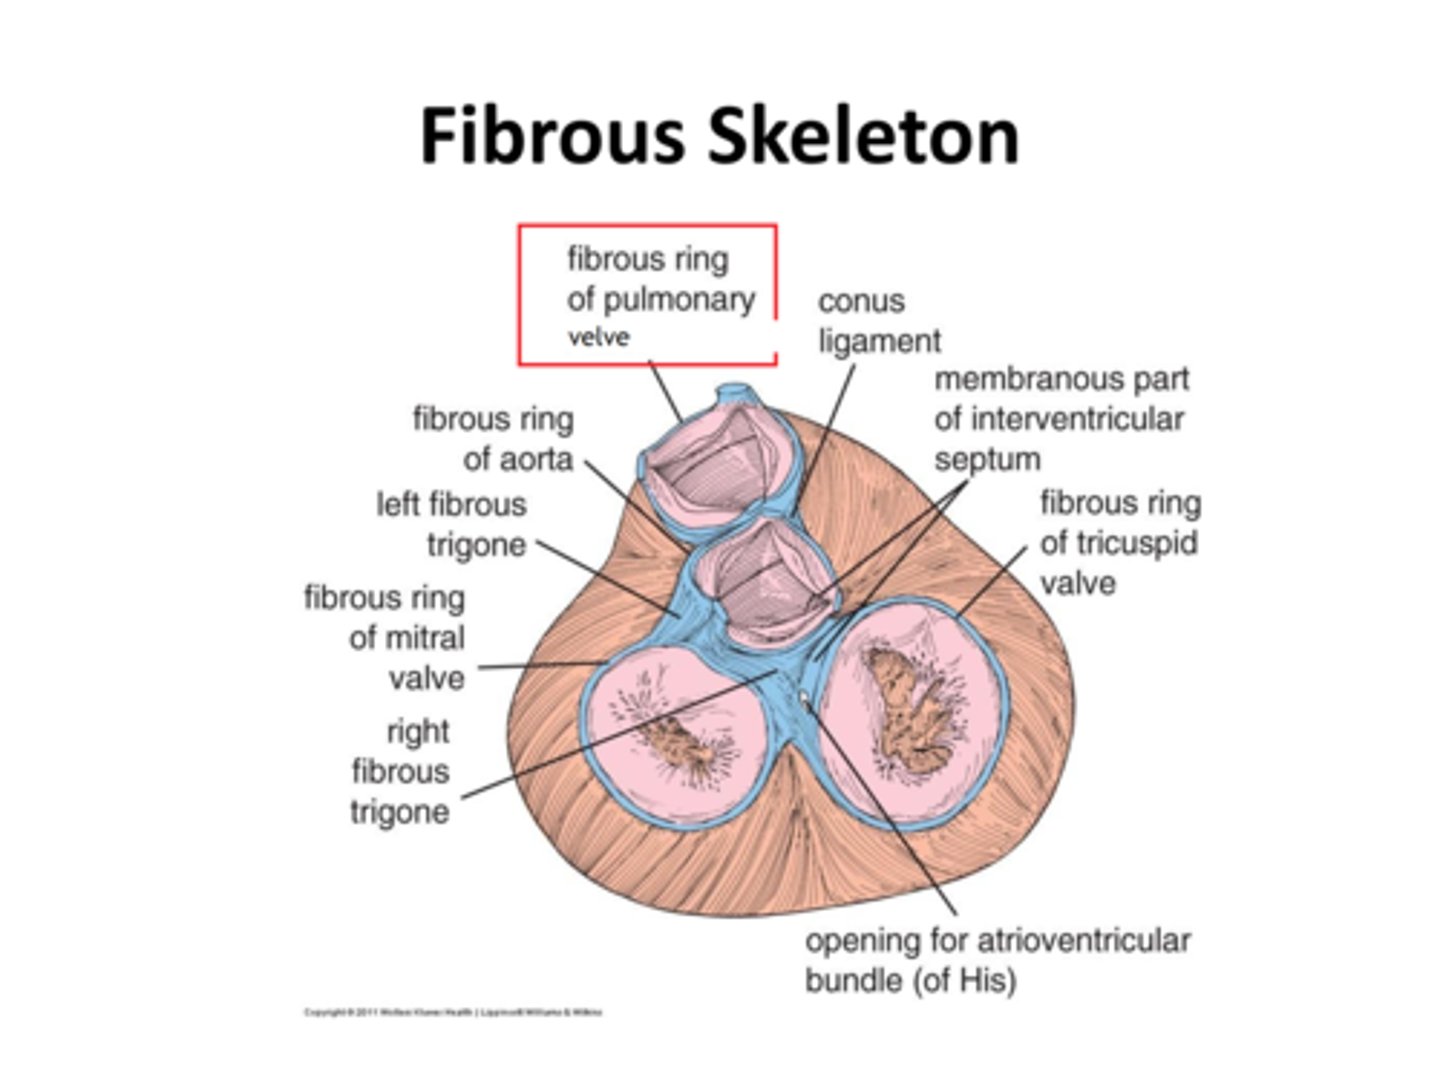

Co tworzy szkielet serca?

tkanka łączna zbita

Jaka jest rola szkieletu serca?

jest miejscem przyczepu mięśniówki przedsionków i komór oraz zastawek

Jakie są elementy szkieletu serca?

4 pierścienie włókniste

2 trójkąty włókniste

część błoniasta przegrody międzykomorowej

Jakie pierścienie włókniste wyróżniamy?

pierścień włóknisty pnia płucnego

pierścień włóknisty aorty

pierścień włóknisty przedsionkowo-komorowy prawy i lewy

pierścień włóknisty pnia płucnego

pulmonary ring (fibrous ring of pulmonary valve)

Gdzie znajduje się pierścień włóknisty pnia płucnego?

z przodu

pierścień włóknisty aorty

aortic ring (fibrous ring of aorta)